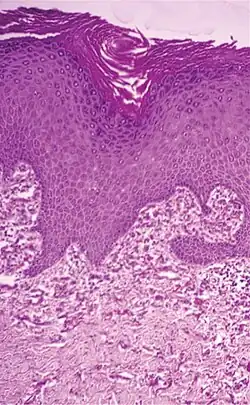

| Elastosis perforans serpiginosa | Degenerated elastic fibers and transepidermal perforating canals (arrow in image points at one of them)[18] |

|